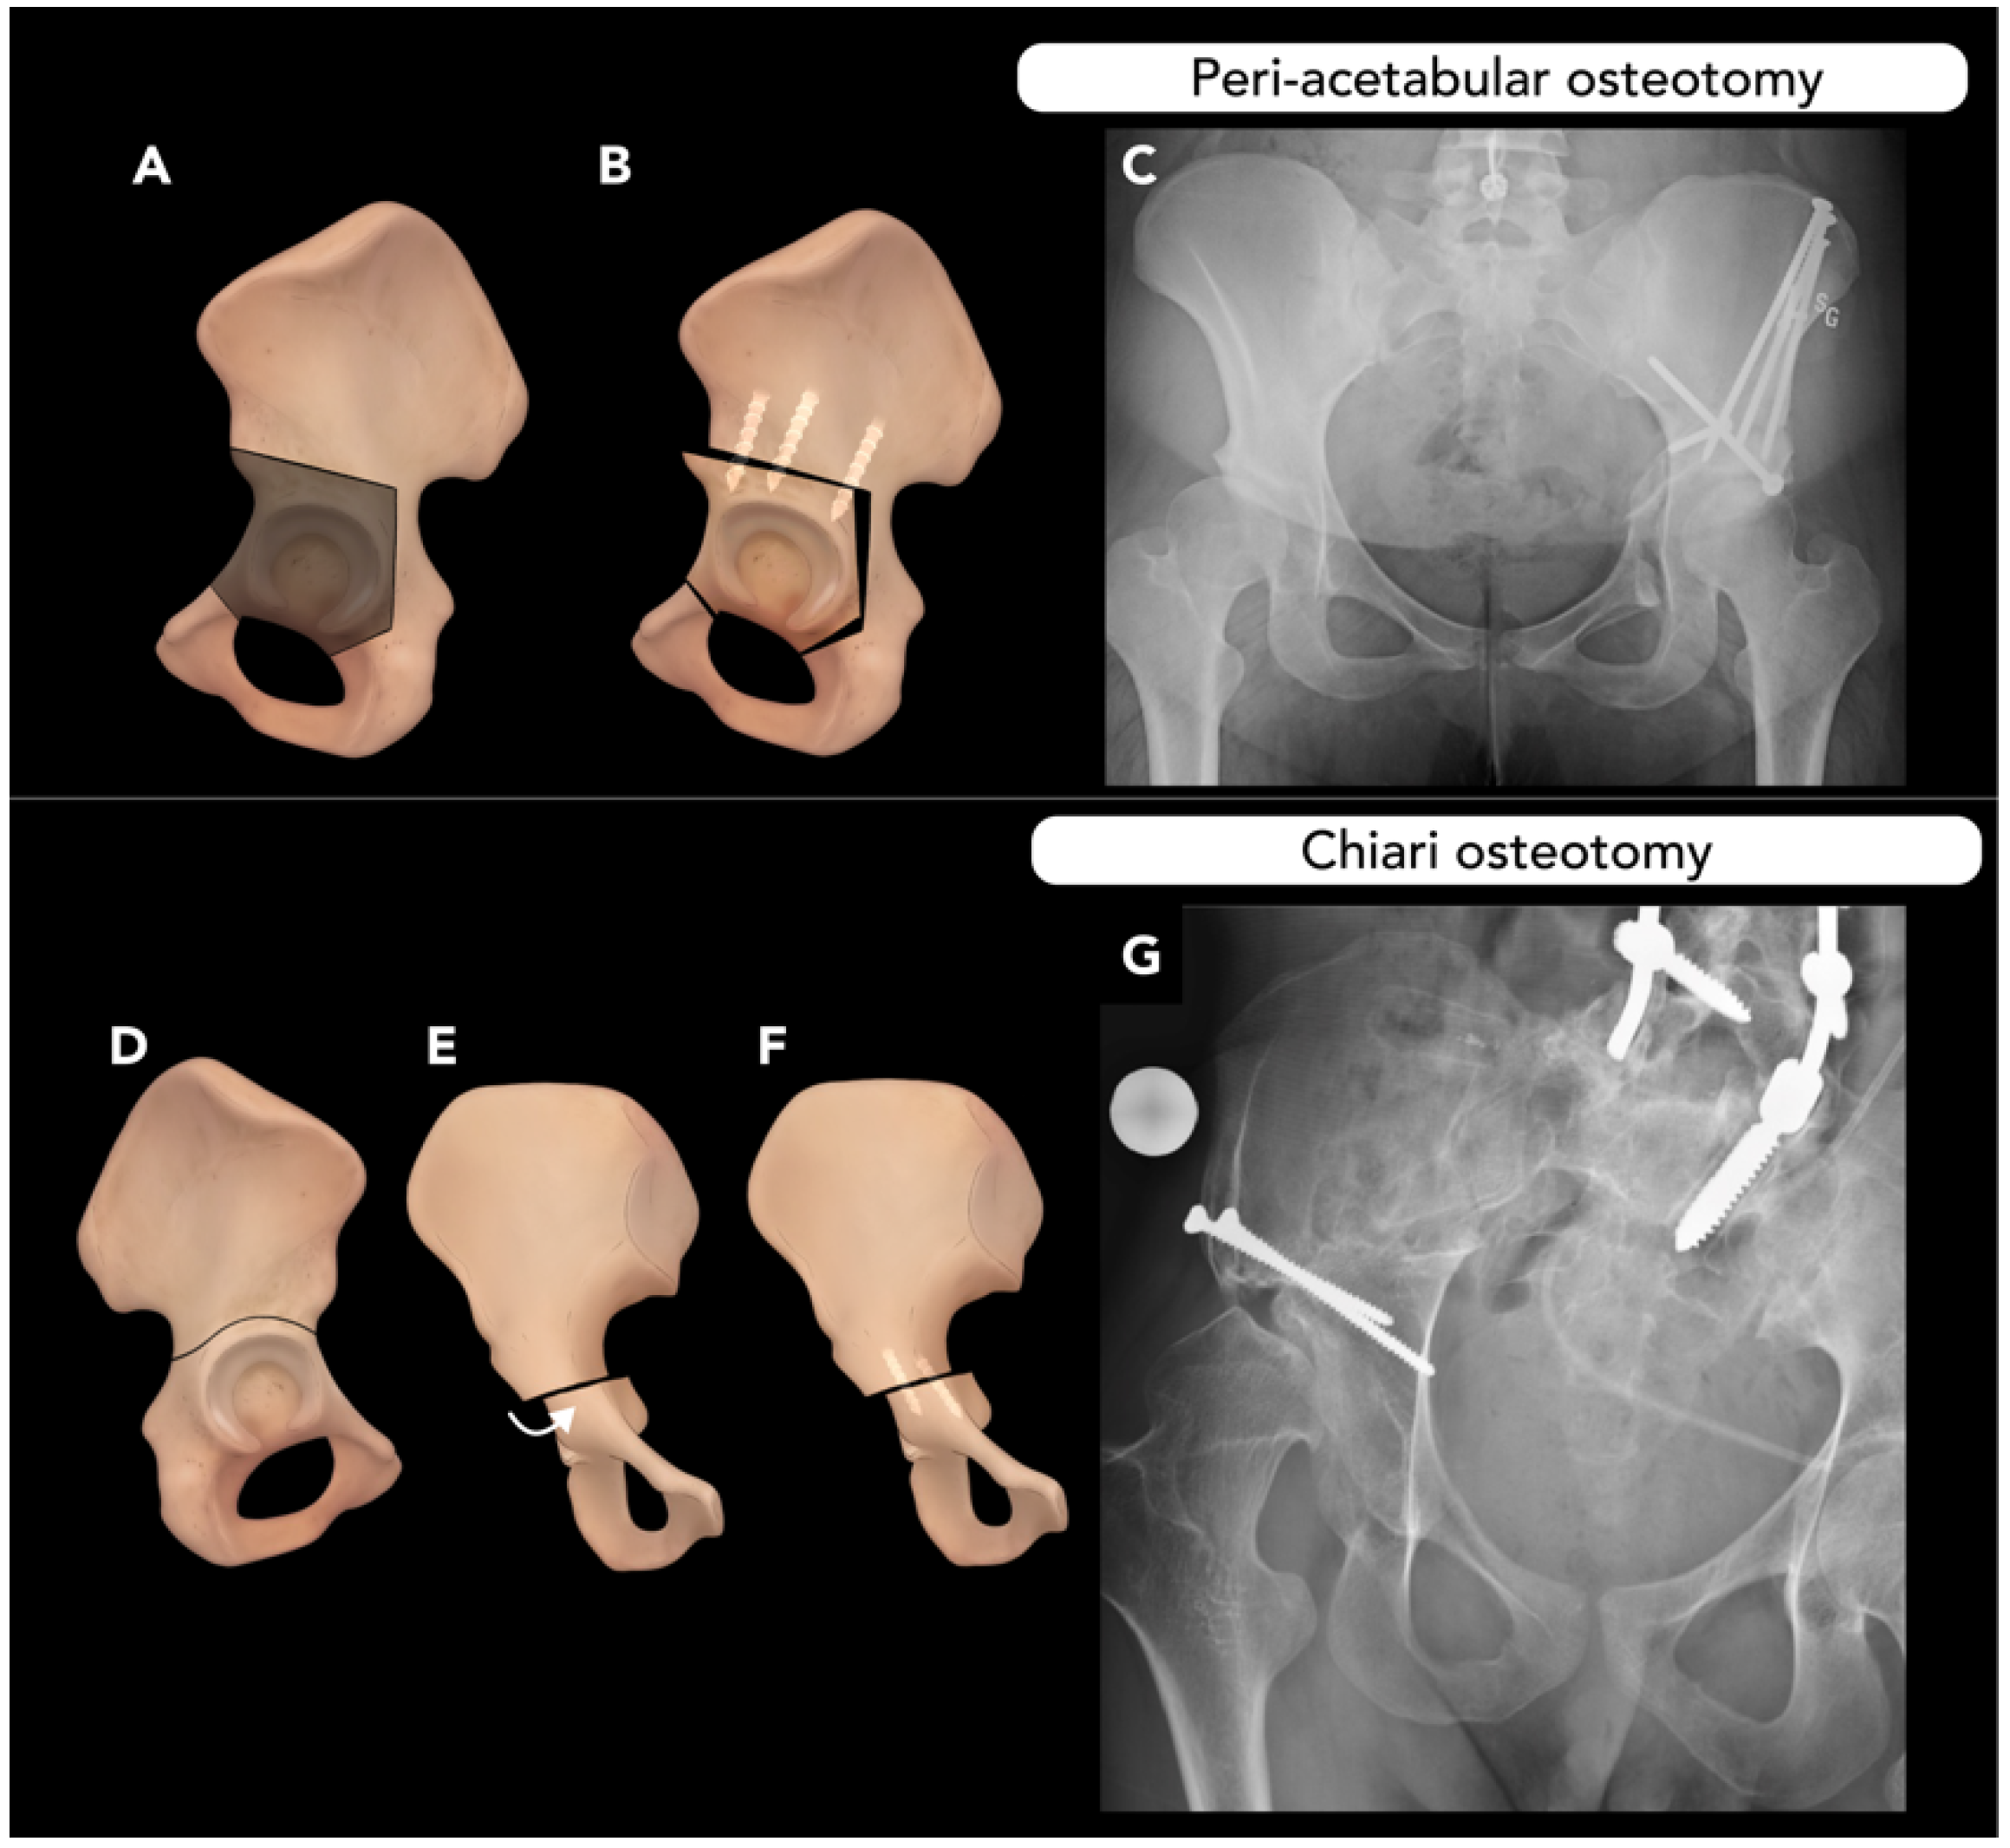

2.4. Pelvic Osteotomy

- Venkatadass, K.; Prasad, V.D.; Al Ahmadi, N.M.M.; Rajasekaran, S. Pelvic osteotomies in hip dysplasia: Why, when and how? EFORT Open Rev. 2022, 7, 153–163. [Google Scholar] [CrossRef]

- Starr, V.; Ha, B.Y. Imaging update on developmental dysplasia of the hip with the role of MRI. Am. J. Roentgenol. 2014, 203, 1324–1335. [Google Scholar] [CrossRef] [PubMed]

- Mills, M.K.; Strickland, C.D.; Jesse, M.K.; Lowry, P.A.; Mei-Dan, O.; Flug, J.A. Postoperative imaging in the setting of hip preservation surgery. Radiographics 2016, 36, 1746–1758. [Google Scholar] [CrossRef]

- Beck, M.; Lash, N.J.; Ganz, R. Surgical Technique: Periacetabular Osteotomy. In Hip Arthroscopy and Hip Joint Preservation Surgery; Springer: Berlin/Heidelberg, Germany, 2022; pp. 663–682. [Google Scholar]

- Hsu, J.-Y.; Lee, C.-C.; Lin, S.-C.; Wang, T.-M.; Kuo, K.N.; Wu, K.-W. Radiographic outcomes of ganz versus modified triple osteotomies in femoral head medialization and coverage in acetabular dysplasia. J. Clin. Med. 2022, 11, 1924. [Google Scholar] [CrossRef] [PubMed]

- Shibata, K.R.; Matsuda, S.; Safran, M.R. Open treatment of dysplasia—Other than PAO: Does it have to be a PAO? J. Hip Preserv. Surg. 2017, 4, 131–144. [Google Scholar] [CrossRef]

- Vrgoč, G.; Bulat, S.; Vuletić, F. Role of Chiari osteotomy in treating degenerative hip arthritis: A review. J. Clin. Orthop. Trauma 2022, 24, 101687. [Google Scholar] [CrossRef]

- Weber, M.-A.; Egermann, M.; Thierjung, H.; Kloth, J. Modern radiological postoperative diagnostics of the hip joint in children and adults. In RöFo-Fortschritte Auf Dem Gebiet der Röntgenstrahlen und der bildgebenden Verfahren; Georg Thieme Verlag KG: Stuttgart, Germany, 2015; pp. 525–542. [Google Scholar]